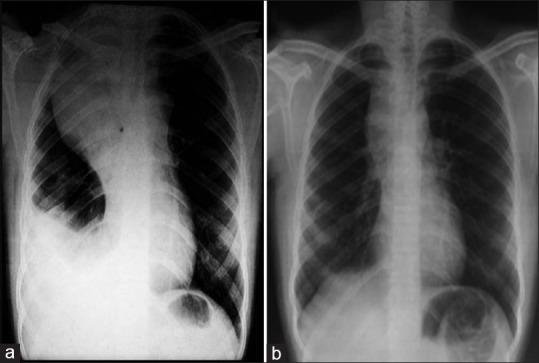

Mediastinal masses are commonly encountered in clinical practice. The commonly encountered anterior mediastinal masses include those of thymic or thyroid origin, teratomas, and lymphoma. Establishing the diagnosis by histopathology is essential considering the wide range of differential diagnosis and to exclude malignancies. Here, we present an unusual case of large mediastinal mass with chylothorax in a young immunocompetent female.